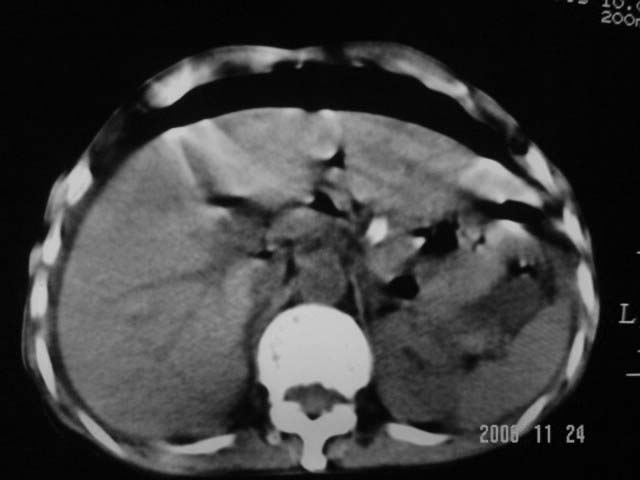

仰卧位见:肝前间隙及肝脾间隙内可见新月形气体密度影,边缘清楚,侧卧位见气体随体位改变而移动,ct值约-929hu。膈下、肝下间隙及部分肠间隙可见液性密度影。考虑:1、上腹部空腔脏器穿孔,以胃穿孔可能性大。2、少量腹水。

仰卧位见:肝前间隙及肝脾间隙内可见新月形气体密度影,边缘清楚,侧卧位见气体随体位改变而移动,ct值约-929hu。膈下、肝下间隙及部分肠间隙可见液性密度影。考虑:1、上腹部空腔脏器穿孔,结合临床,首先考虑胃穿孔可能性大。2、少量腹水

腹腔积液,气腹.空腔脏器穿孔!

可见游离气体,上消化道穿孔,少量腹水,腹膜炎